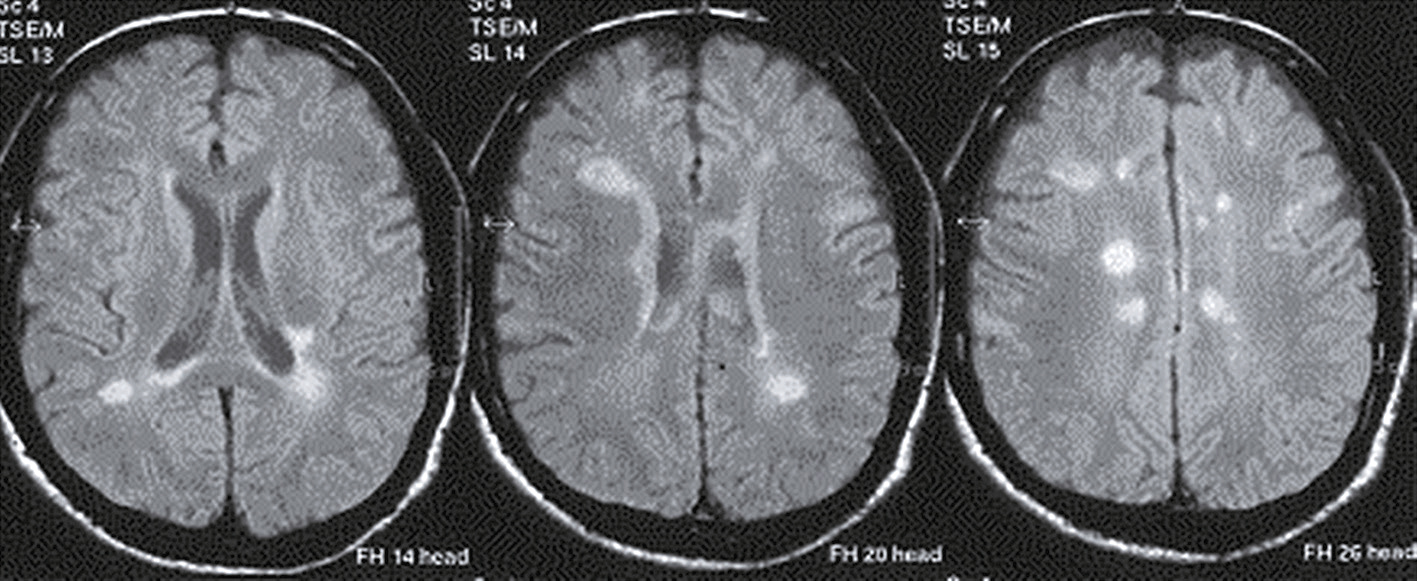

Une IRM encéphalique est réalisée (fig. 31.7). Sur cette planche, quels sont les éléments évocateurs du diagnostic de sclérose en plaques (SEP) ?

L'image montre trois coupes transversales d'un cerveau humain prises par imagerie par résonance magnétique (IRM). Chaque coupe est étiquetée avec des informations spécifiques : "FH 14 head", "FH 20 head" et "FH 26 head". Ces étiquettes indiquent probablement différentes sections ou niveaux de la tête. Les images montrent des zones de signal hyperintense, qui apparaissent comme des taches blanches sur les images. Ces zones peuvent indiquer des anomalies telles que des lésions, des plaques ou d'autres types de pathologies cérébrales. Les coupes transversales permettent de visualiser différentes parties du cerveau, y compris les ventricules cérébraux et la matière blanche environnante. Les images sont intéressantes car elles permettent de détecter et de surveiller des conditions neurologiques, d'évaluer l'étendue des dommages et de planifier des traitements appropriés. Les variations dans les images peuvent fournir des informations cruciales sur la progression de la maladie ou l'efficacité des interventions thérapeutiques.

- A 585présence d’hypersignaux de la substance blanche

- B localisation surtout périventriculaire des hypersignaux

- C aspect arrondi des hypersignaux

- D présence de trous noirs

- E atrophie cérébrale marquée